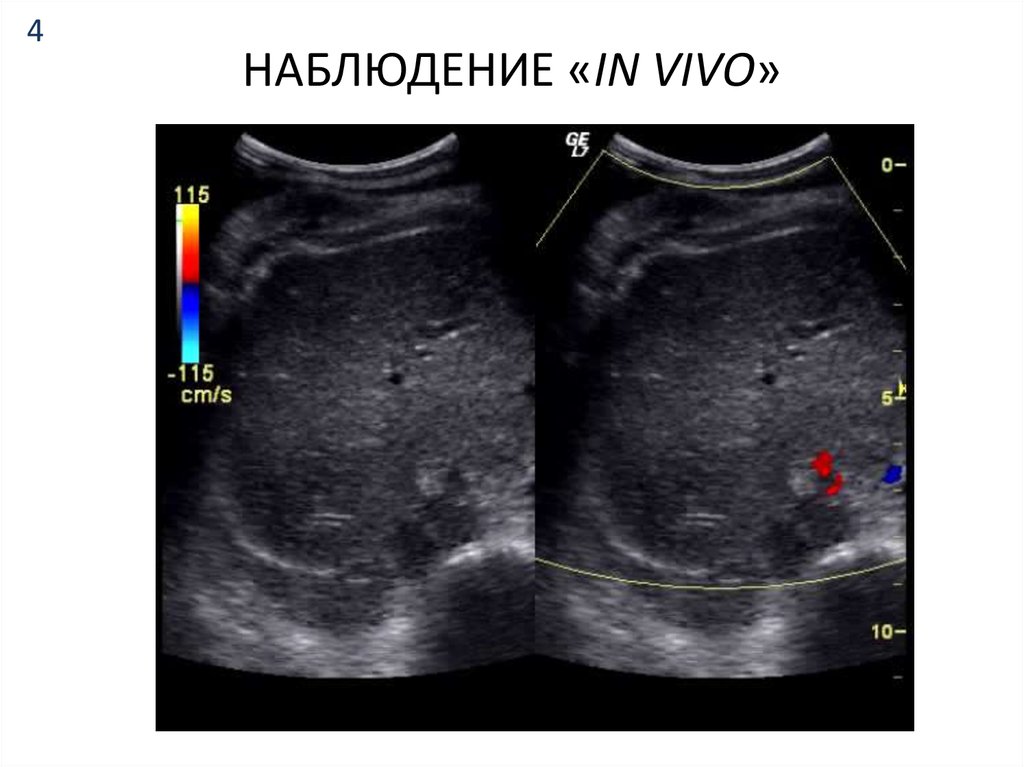

4. НАБЛЮДЕНИЕ «IN VIVO»

НАБЛЮДЕНИЕ «IN VIVO»